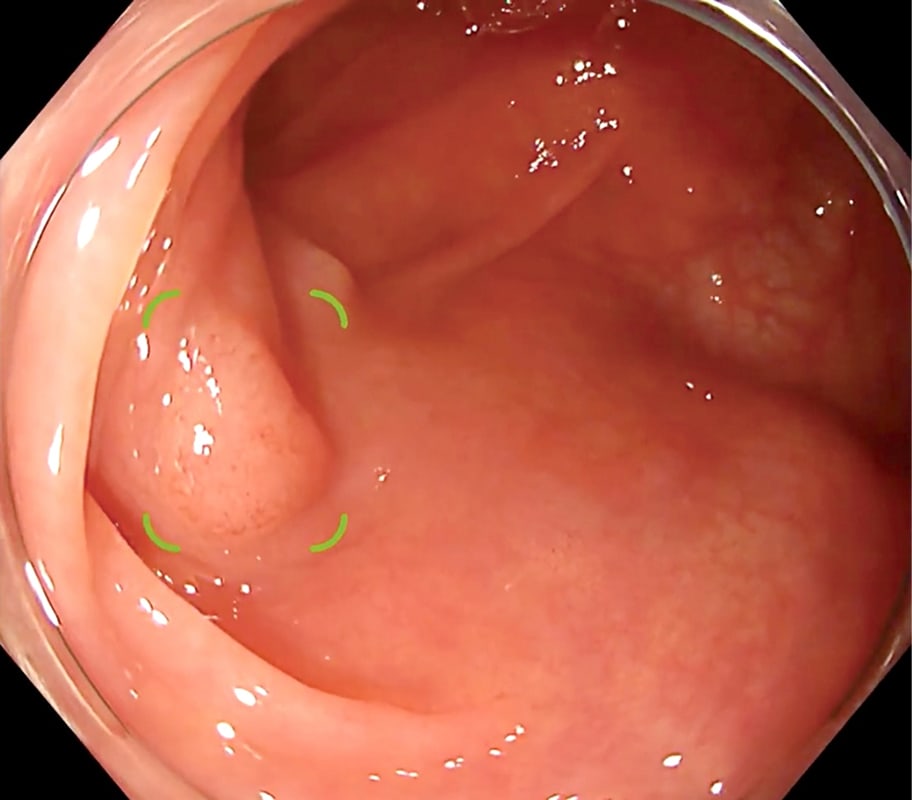

Chest nodule detection support technology that makes an effective diagnosis possible

EIRL Chest Nodule supports the interpretation process by identifying findings suggestive of lung nodules from chest X-rays that are larger than 5 mm and smaller than 30 mm. The sensitivity of the specialized-radiologist and the non-specialized radiologist interpreting the images with the software increased by 9.9% and 13.1 % respectively, suggesting an improvement in diagnostic accuracy.